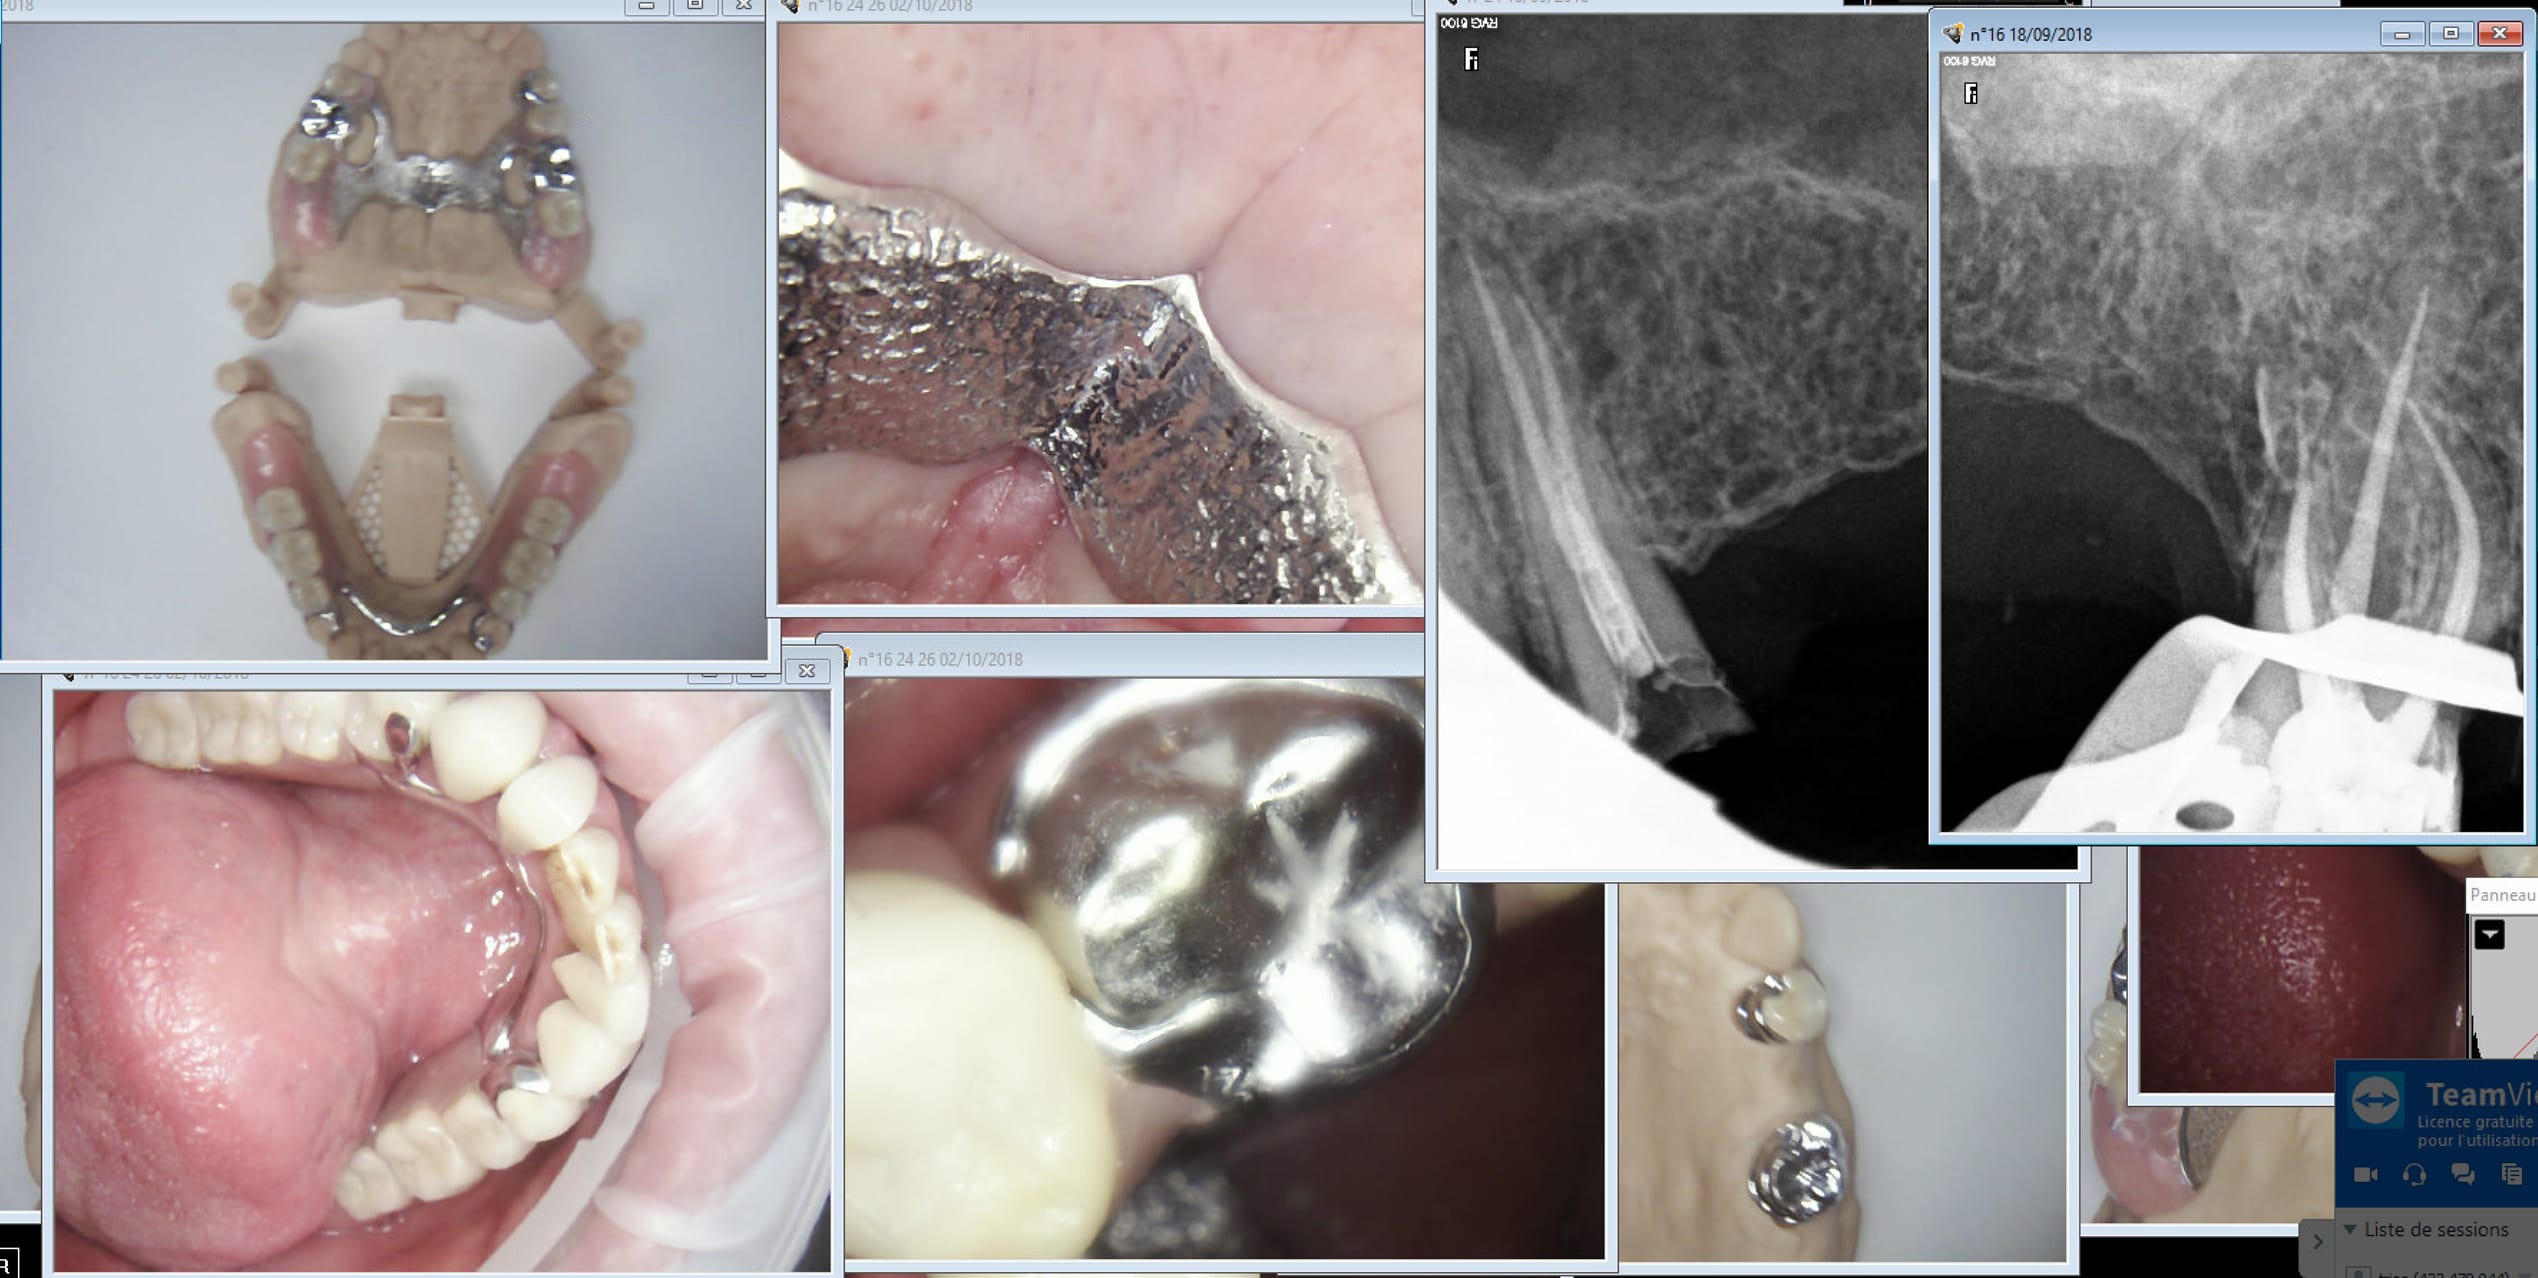

ces réalisation low cost ne sont pas à mettre à l'honneur ni de la partielle ni des des réalisations CAD CAM .....

la partielle vaut mieux que cela ....

??? Bon, je fais un ou deux partiels amovibles par an et 0 complet, et j'y connais rien. Cependant j'en vois régulièrement dans la bouche des patients, les appareils sont en général très vieux, usés et ils ressemblent plus ou moins à ça.

à titre d'informations complémentaires

1. les modèles présentés sont MADE IN FRANCE

2. Le nombre de prothèse partielles réalisées annuellement en France est de 1 300 000 ....

les derniers cas montrent que cela ne s'améliore pas .....

Effectivement. De la daube. Ces glands m'ont meme fait de la fixe en meme temps qu'une finition directe du stellite. -)))

Bah c'est assorti avec les endos-peintures canalaires à la française à un tarif de merde sécu sous jacentes. Tu trouves pas ?

Je ne vois pas bien le rapport entre CAD CAM et stelitte de merde !

Log69 tu voudrais dire que la gestion numérique des empreintes et de la conception de ce type de prothèse serai codée pour fournir de la merde, photos à l'appui comme preuve?

La prothése partielle à châssis métallique est un domaine plutôt délaissé dans la formation continue et pas mal de nos confrères ne s'y intéressent pas le moins du monde, et au final les prothésistes suivent la demande: simple et pas cher, le CAD CAM va encore simplifier cette situation par l'amélioration des empreintes et des enregistrements inter maxillaire. Simplification extrême puisque la précision d'une finition direct issue d'une seule empreinte est époustouflante. Mais si la demande et la formation des praticiens n'évolue pas vers une conception de châssis et supports plus abouti, il n'y a pas de raison pour que la qualité progresse.

Ton constat n'a rien à voir avec la CAD CAM (bien au contraire), mais avec le désintérêt de notre profession pour ce type de prothèse,

Je comprends pas bien l'intérêt de tes posts.

Tu balances une photo d'un modèle et ...... rien.

Sur un autre post, tu balance une pano et ........rien.

Y'a rien qui suis, pas de démarche clinique, pas d'objectif thérapeutique, pas de truc de dentistes quoi.

Et pis évaluer la qualité d'une prothèse sur un modèle en plâtre, comment dire....

Ben c'est en bouche que ça s'évalue, tu peux me montrer une super prothèse complète bimax sur un articulateur ou un bridge complet sur son modèle que ça m'en cognerait une sans toucher l'autre.

en réponse aux questions posées:

1. il est facile de voir les insuffisances des réalisations, absence d'appuis et donc de logettes, conceptions erronées, ...

2. ce constat s'applique à toutes les prothèse faites de façon conventionnelle ou en CAD CAM

3. le CAD CAM aggrave la situation car toutes ces prothèses sont réalisées sans tracé préalable et donc sans préparation de la bouche, ce qui est la négation de la partielle

4. le seul objectif est de faire la prothèse en deux temps,, sachant les insuffisances d l'empreinte globale en bouche, on fait rêver les ignorants !